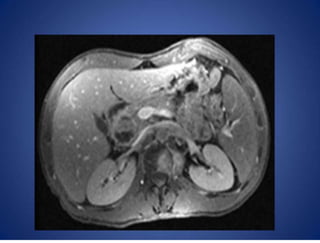

Computertomographyscan

Loculated ascites

46